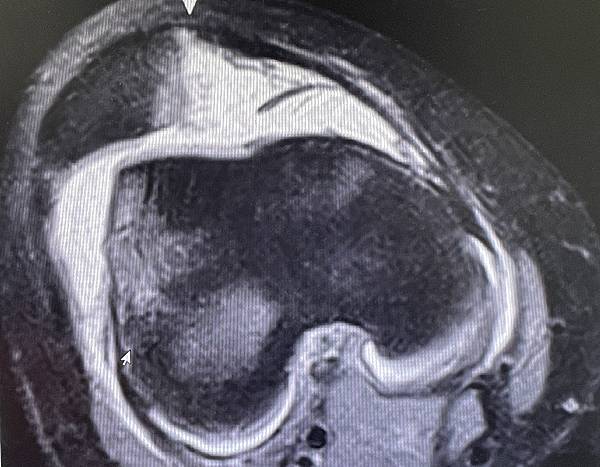

膝關節內側髕骨股骨韌帶斷裂MRI